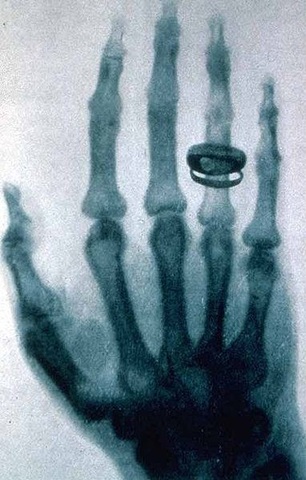

• Primera Radiografía

Primera Radiografía

La primera radiografía fue la mano de su esposa de Roentgen